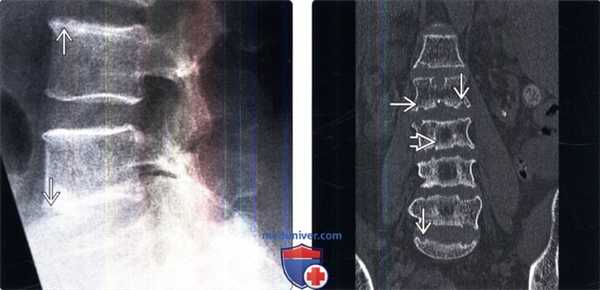

(Слева) Рентгенография в боковой проекции: признаки диффузной неспецифической остеопении. Ключевым признаком в пользу диагноза ГПТ являются эрозии замыкательных пластинок, которые, однако, могут наблюдаться и при инфекционном поражении, болезни накопления пирофосфата кальция, почечной остеодистрофии или при дегенерации межпозвонкового диска. Изменения на двух несмежных уровнях, как в этом случае, делает диагноз инфекции маловероятным.

(Справа) Фронтальный КТ-срез: множественные эрозии замыкательных пластинок на фоне гиперпаратиреоза (ГПТ). Бедность трабекулярного рисунка центральных отделов позвонка от опухолевого поражения отличает характер МР-сигнала в этих зонах, который соответствует нормальной жировой ткани.

(Слева) Сагиттальный КТ-срез: признаки тяжелого гиперпаратиреоза у 50-летнего пациента. Первичные (вертикальные) трабекулы ярко выражены, что связано с резорбцией вторичных трабекул. Видны многочисленные грыжи Шморля и патологический перелом Т12.

(Справа) Фронтальный КТ-срез, этот же пациент: эрозии крестцово-подвздошных суставов. Это достаточно распространенная при ГПТ находка, однако именно она может привести к постановке неверного диагноза анкилозирующего спондилита.